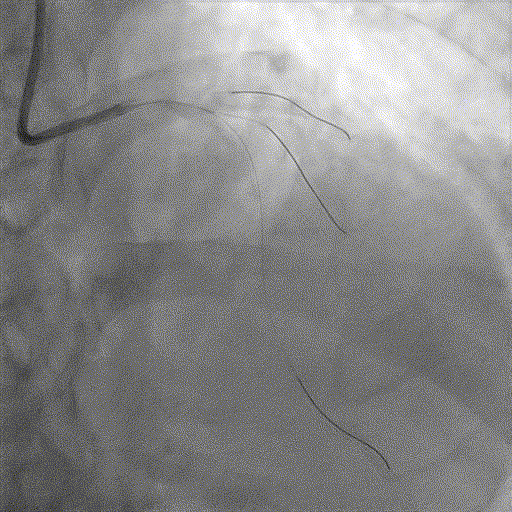

手术经过

导丝到位

当指引导管冠脉开口到位后,选择三根对应导丝分别送入LAD、D1、D2远端。

球囊预扩

选择不同尺寸的预扩球囊逐级预扩张病变,复查造影狭窄减轻不明显。为了解血管真实情况,遂启用IVUS检查。

术前腔内影像学IVUS指导

IVUS提示血管内钙化严重,最小管腔面积不足 4mm²;遂考虑启动IVL治疗。

冲击波球囊治疗

2.5*12mm@4atm 冠脉血管内冲击波导管反复进行8个周期治疗,经IVUS检查提示最小管腔面积增加至4.88mm²;随后选取后扩张球囊对病变行扩张治疗。

支架植入并后扩

于LM-LAD依次植入两枚药物洗脱支架,经非顺应性球囊后扩张支架,复查造影&IVUS提示血管内钙化仍较重,支架贴壁不良,遂再次启动IVL治疗。

再次冲击波球囊治疗

3.0*12mm@4atm 冠脉血管内冲击波导管反复进行5个周期治疗,并选取后扩张球囊对病变行扩张治疗。最终复查造影提示残余狭窄小于10%,未见夹层及血肿,TIMI血流3级。